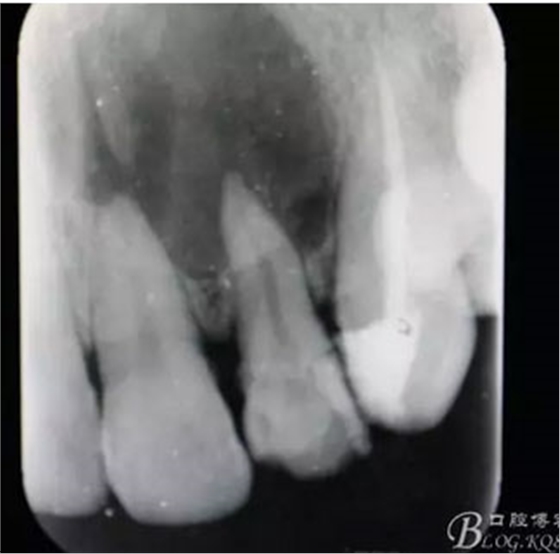

圖1.術(shù)前患者的x光根尖片檢查影像:22根尖完全位于囊腔內(nèi),牙槽骨吸收至嵴頂約5mm。22松動(dòng)Ⅰ度。